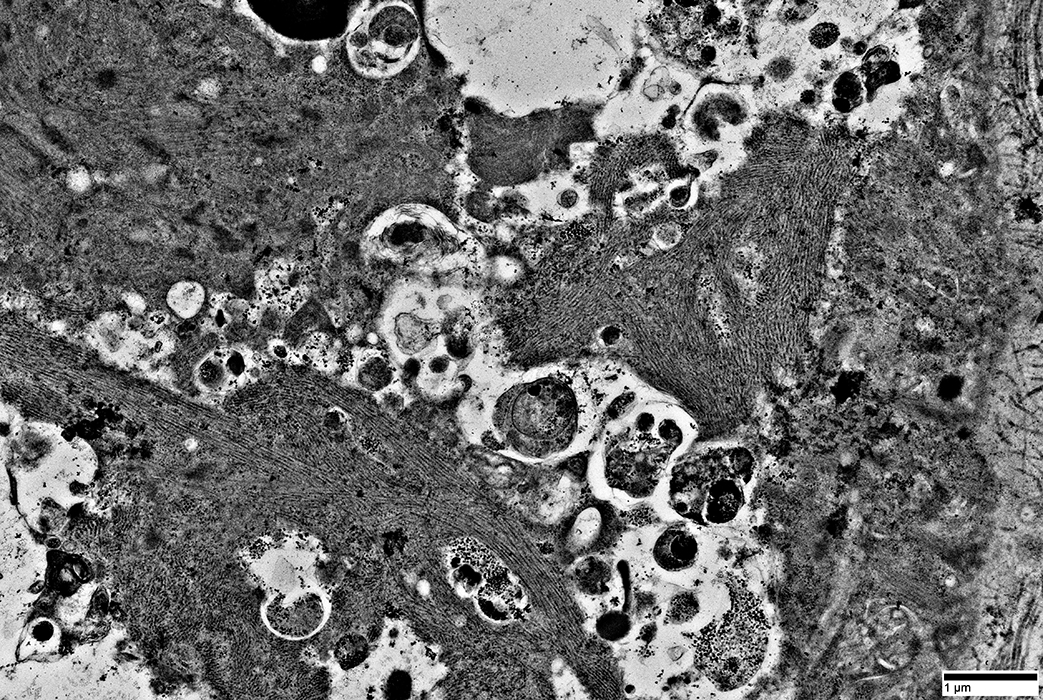

Mitochondria: Abnormal morphology

Mitochondria are often

Elongated

Irregular shaped

From: R Schmidt

|

Mitochondria: Elongated

Mitochondria: Increased Numbers

Mitochondrial pathology: Subsarcolemmal regions

Some areas have dense collections of mitochondria (Left)

Other subsarcolemmal areas have relatively few mitochondria (Right)